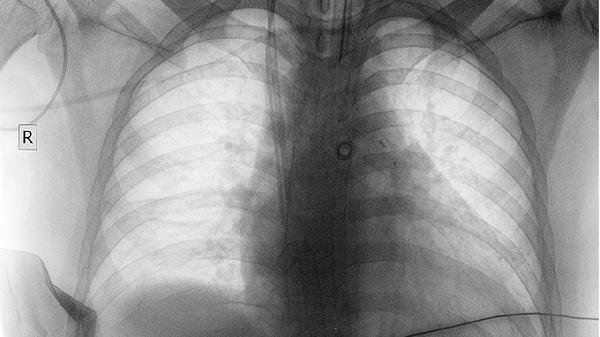

肺結(jié)節(jié)發(fā)展為肺癌通常需要5-20年,具體時(shí)間與結(jié)節(jié)性質(zhì)、個(gè)體差異及生活習(xí)慣密切相關(guān)。

肺結(jié)節(jié)演變?yōu)榉伟┑臅r(shí)間跨度較大,多數(shù)情況下這一過(guò)程較為緩慢。良性結(jié)節(jié)或穩(wěn)定性結(jié)節(jié)可能長(zhǎng)期保持原狀甚至自行消退,惡性風(fēng)險(xiǎn)較低的磨玻璃結(jié)節(jié)往往進(jìn)展遲緩,部分微浸潤(rùn)癌發(fā)展周期可達(dá)10年以上。影響進(jìn)展速度的因素包括結(jié)節(jié)初始尺寸與密度,直徑不足8毫米的實(shí)性結(jié)節(jié)惡性概率較低,直徑超過(guò)15毫米的混合磨玻璃結(jié)節(jié)需提高警惕。個(gè)體免疫狀態(tài)與遺傳背景也會(huì)干預(yù)進(jìn)程,存在肺癌家族史或長(zhǎng)期吸煙史的人群轉(zhuǎn)化時(shí)間可能縮短。環(huán)境暴露因素如持續(xù)接觸石棉粉塵或放射性物質(zhì)可能加速細(xì)胞異變。定期隨訪中若發(fā)現(xiàn)結(jié)節(jié)直徑年增長(zhǎng)超過(guò)2毫米或出現(xiàn)分葉、毛刺等特征,往往提示需要加強(qiáng)監(jiān)測(cè)頻率。